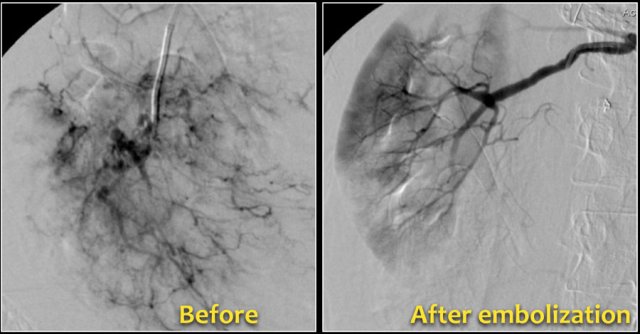

Bleeding in Angiomyopiloma

Due to the abnormal vessels within an AML, it is prone to bleeding.

Patients can present with acute flank pain due to spontaneous hemorrhage.

The risk of hemorrhage increases with size.

Embolization was performed to stop the bleeding.

Preventive embolization is recommended in tumors larger than 4 cm, even in asymptomatic patients.

Notice the large vessels in the AML in the left kidney.